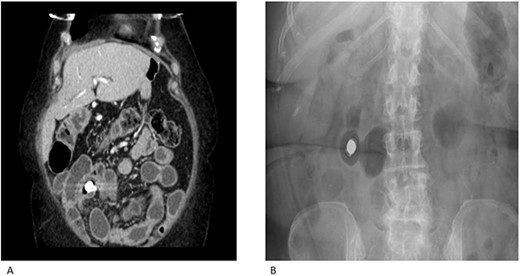

A 69-year-old female had previously undergone a sleeve gastrectomy and Roux-en-Y bypass. She was initially seen in the Haematology clinic with iron deficiency anaemia presumed secondary to her gastric bypass. Upper and lower GI endoscopy were within normal limits. She was managed with iron infusions. Of note, the patient had been on diclofenac for several years due to chronic back pain. Few months later she was reviewed in the cardiology clinic for shortness of breath on exertion and referred to gastroenterology due to her low albumin and haemoglobin. Repeat gastroscopy was normal and colonoscopy demonstrated ulcerations on the ileocaecal valve thought to be secondary to diclofenac use. She underwent a capsule enteroscopy that demonstrated a grossly abnormal distal ileum with a series of tight ulcerated strictures (Fig. 1). A CT of the abdomen and pelvis demonstrated multiple areas of mid small bowel stricturing and a further segment of terminal ileal abnormality. There was some evidence of deep ulceration and a diagnosis of Crohn’s disease remained on top of the list of differentials due to the presence of ulceration and skip lesions. The capsule from her enteroscopy was noted to be stuck within the small bowel (Fig. 2). The patient subsequently underwent ileo-caecectomy, on table stricture dilation and stricturoplasty. Histology demonstrated multiple small bowel ulcers with focal structuring and multiple small intramural diverticulae. No evidence of Crohn’s disease. NSAIDs were the most probable cause of the histologic appearance. The patient was advised to stop consuming NSAIDs and made a slow recovery thereafter.

CT enterography (A) and plain X-ray (B) demonstrating multiple areas of mid small bowel stricturing. Some evidence of deep ulceration and skip lesions. Of note, the capsule remains stuck within the small bowel and is at risk of causing obstruction.